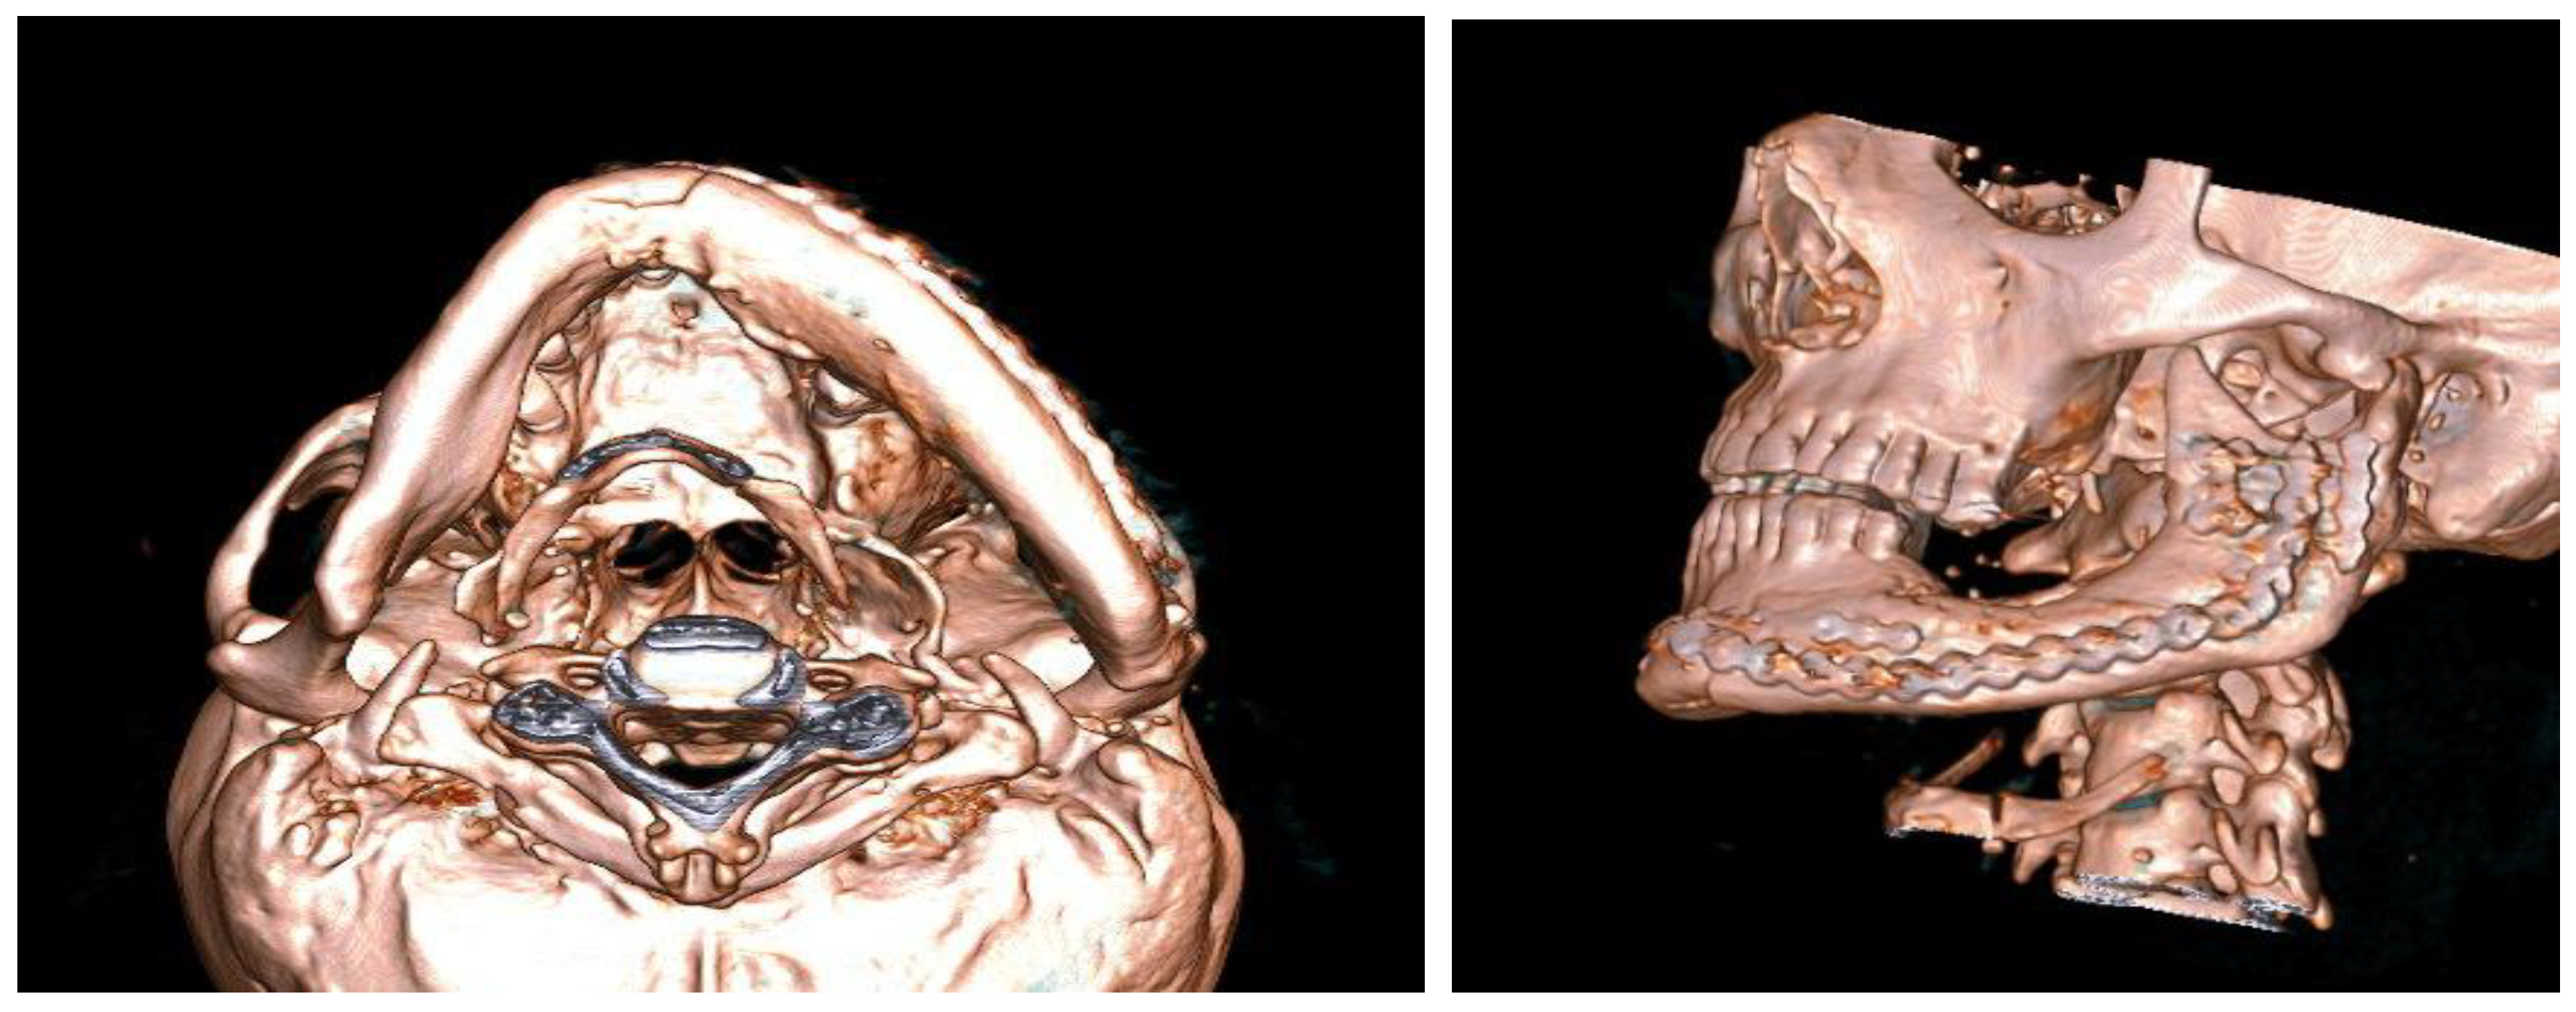

- phase 1: Conversion of the CT scan of the mandible from DICOM format to a 3D STL model

- phase 2: Model of the deformed part of the mandible before and after computer-assisted resection

- phase 3: Computer modeling of the implant

- phase 4: Comparison of the previous state of the mandible and the reconstruction